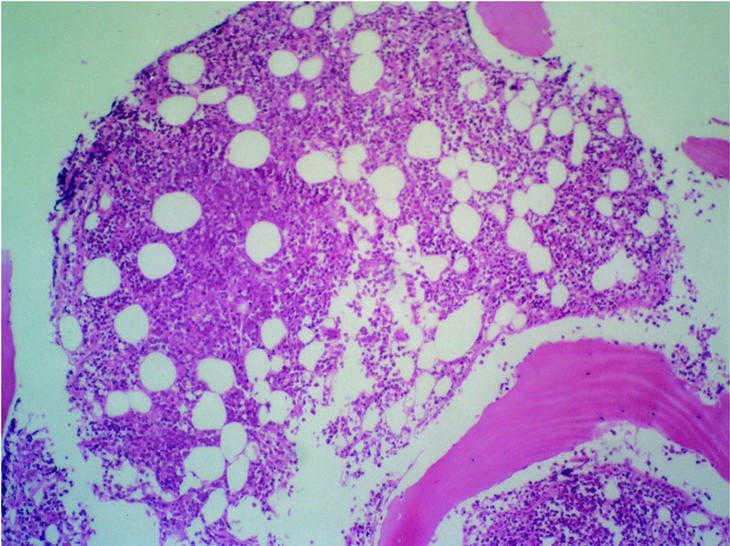

Fig. 5. Cilindro de médula ósea que presenta una celularidad hematopoyética conservada con una buena distribución entre el parénquima y la grasa con presencia de las tres series que muestran una arquitectura dentro de los límites de la normalidad. Se identifican megacariocitos de pequeño tamaño y núcleo hipercromático. Focalmente se observa infiltración del espacio medular por una celularidad linfoide de gran tamaño, núcleo vesiculoso, cromatina grumosa y nucleolo prominente que se dispone formando un nódulo paratrabecular.

Fig. 6. Estudio de inmunohistoquímica sobre material parafinado en el que se observa que la celularidad linfoide de gran tamaño descrita resulta positiva para marcadores Pan-B (CD20) y negativos para marcadores Pan-T (CD3). El índice de proliferación en la celularidad linfoide medido como positividad nuclear con Mib-1 es superior al 75% de las células.